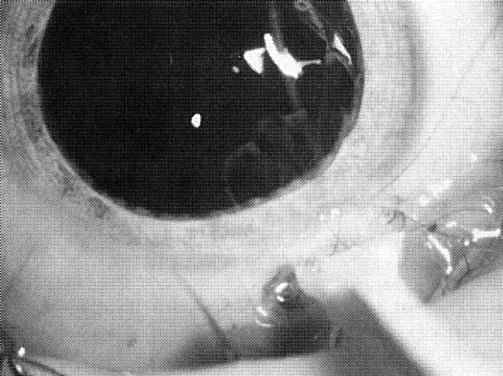

Eyes with pediatric cataracts appear to have an abnormal outflow facility and a propensity for open-angle glaucoma. Simon and colleagues52 reported glaucoma in 24% of eyes treated for cataracts and followed for at least 5 years. Johnson and Keech53 reported glaucoma in 32% of patients with PHPV-type cataracts (eight of 25) and the same 32% in patients with infantile cataract (15 of 47). The mean time of onset of glaucoma was 65 months and 47 months after surgery, respectively. Chrousos and associates38 found chronic glaucoma in 6.1% of treated eyes. Eyes with rubella, uveitis, or microphthalmia are particularly affected. A slightly more anteriorly placed incision and careful wound closure prevent iris-to-cornea adhesions. Figure 31 shows a gonioscopic view of an angle of a 5-year-old child in whom late-onset glaucoma developed after cataract surgery. Walton51 has described a near-constant (96%) but variable angle defect characterized by blockage of the trabecular meshwork by an acquired repositioning of the iris against the posterior trabecular meshwork.